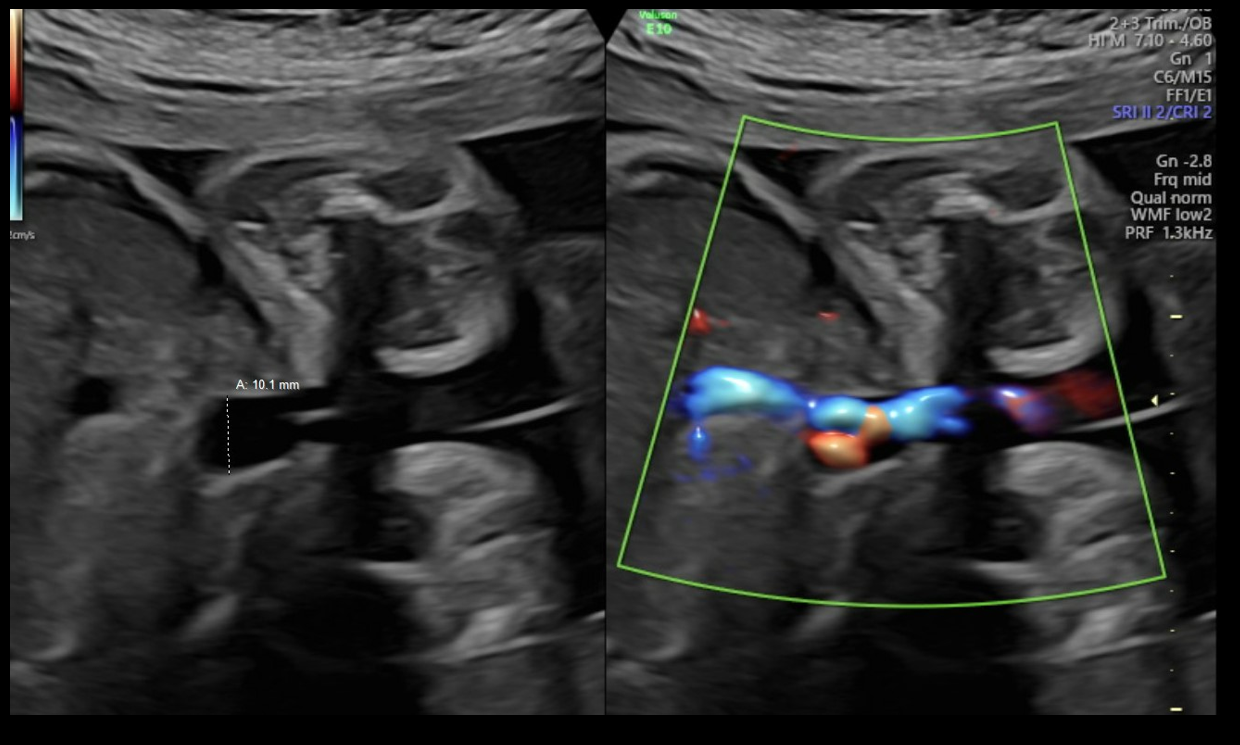

Diagnostic criteria for UVV and the WFUP protocol for subsequent evaluation and surveillance is described in (Table 1) and was followed for all maternal-fetal pairs. UVV characteristics documented during each ultrasound included: size, directionality of blood flow (unidirectional or bidirectional), presence of turbulence, and presence of a filling defect; see (Figures 1a-1c).

Figure 1a. Unidirectional or nonturbulent flow without filling defect.

Figure 1b. Bidirectional or Turbulent flow without filling defect.

Figure 1c. Bidirectional flow with suspected filling defect.

Filling defects were recorded when sonolucent absence of color flow was demonstrated with color Doppler within the UVV. Filling defects were interrogated in transverse and sagittal abdominal views along with color Doppler sweeps to confirm the filling defect and overcome the artifact loss of signal with flow perpendicular to insonation. The presence of UVV and its characteristics was confirmed on repeat ultrasound within 7 days while having monitoring in the interim for fetal well-being. All recorded fetal sonographic measures were uniformly collected by WFUP’s American Institute of Ultrasound in Medicine (AIUM) accredited ultrasound unit by a Registered Diagnostic Medical Sonographer. Voluson E10 General Electric ultrasound machines, with abdominal probe 4-8 and 4 mHz frequency, were used. All WFUP patients are offered genetic counseling and genetic screening as appropriate, including this study’s participants.